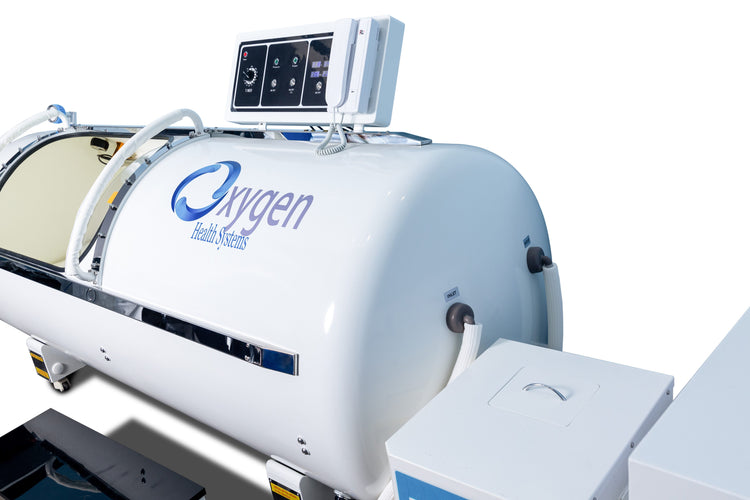

36-Inch Hard Shell Hyperbaric Oxygen Chamber supports 2.0 ATA (100 kPa) pressure and 15 PSI. Built with 2.5 mm thick 304-grade stainless steel and a 10 mm thick polycarbonate window from Bayer Germany. Designed with heavy-duty steel rods and ball-bearing rollers for smooth movement. Features incremental control of pressurization and depressurization, interior and exterior emergency pressure relief valves, interior lighting, and an alarm system. Allows auto-controlled session times up to 2 hours with a timer and offers an optional progressive control feature. Chamber dimensions are 88 inches in length and 36 inches in diameter. Includes a 3-year warranty.